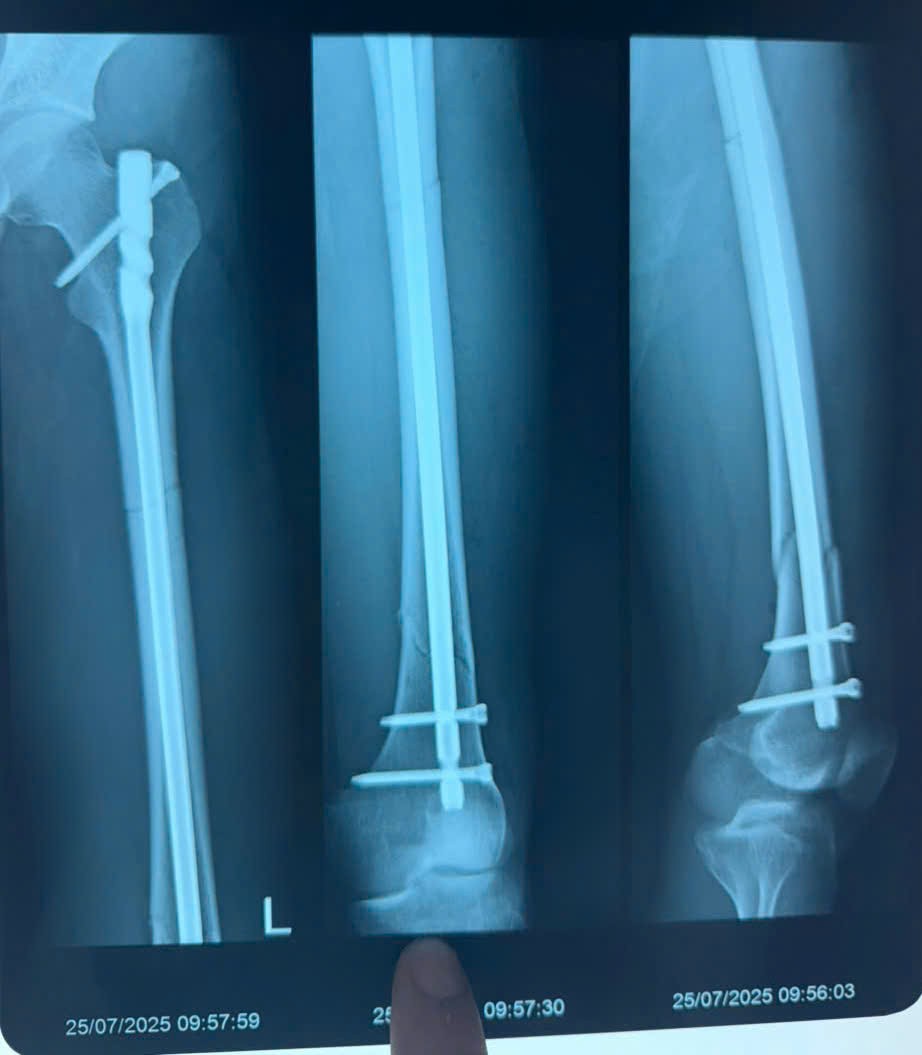

Ca phẫu thuật được thực hiện ngay trong đêm. Với phương pháp kết hợp xương hiện đại, các bác sĩ đã cố định vững chắc phần xương gãy mà không cần mở rộng vùng tổn thương, giúp giảm thiểu sang chấn mô mềm và tối ưu khả năng hồi phục cho bệnh nhân.

| Hình ảnh xương đùi đã được cố định sau phẫu thuật. |